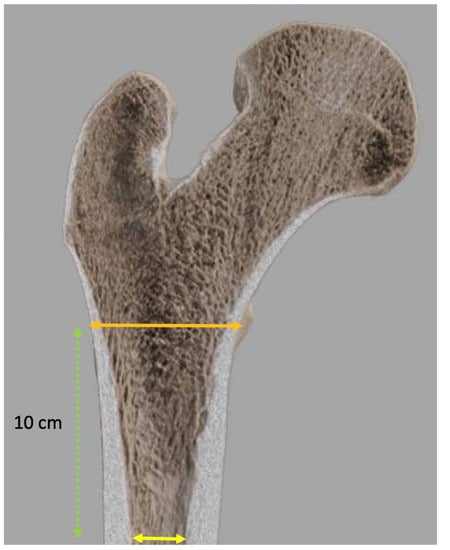

| Width of the endosteal diaphyseal and metaphyseal canal diaphysis | Size of the femoral component |